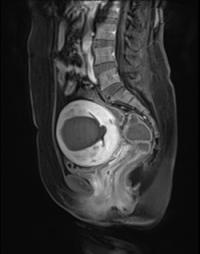

ÀڱñÙÁ¾º¸´Ù ´õ ¹«¼¿î 'Àڱü±±ÙÁõ'

¡ãÀڱü±±ÙÁõ ȯÀÚ MRI (ÇÏÀÌǪ½Ã¼ú ý)[¿Óóµ¥Àϸ®] ´ë°³ ¡®Ä¿...